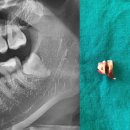

소독 하러 방문하고 일주일뒤엔 실밥 뽑으러 방문..! 사진찍으니 오른쪽 사랑니 없음 ㅎㅎㅎ 왼쪽이 남음 ^_ㅠ... 왼쪽도 왜 매복인게냐,,, 왼쪽은 다음 기회에!! ㅎㅎ ​ 치과 공포증이 있다면 사랑니 발치는 죽파치과 추천합니동 >< ​ #포항죽파치과#죽파치과#사랑니발치#포항사랑니발치#포항사랑니치과#포항사랑님발치후기

피하고만 있던 사랑니 발치 아랫니는 누워서 자라고있는 매복사랑니 애증의 사랑니 몇번이고 맘먹고 포기하다가 드디어 발치에 성공하고 온 후기 정보는 요기⤵️ 💓 죽파치과 💓 ​ 주소: 포항시 북구 중흥로 277 4층 영업시간: 월-금 11:00-20:00 접수마감: 19:15 휴게시간: 16:00-17:00 전화번호: 0507-1405-9899 주차장...

있다면 또 끔찍했을듯 사랑니는 관리도 신경써야하니까요 ㅠㅠㅠ 다음날 간단후기 ​ 잠은 생각보다 잘잤음 아파서 깬것은 아니고 얼음찜질 압박감에 두번정도 깸...붓기는 절개가 아니여서 그런지 말안하면 모를듯 알면 보임 ​ 포항 죽파치과 빠르고 안아프게 발치 잘하셔요 소문듣고 찾아가길 잘했고 당일 상담 당일 발치...

포항 죽파치과를 방문했습니다. 왼쪽 위아래 사랑니(사진상 오른쪽 위아래) 🏥 첫 방문 – CT 촬영 & 발치 가능 여부 확인 첫째 날은 퇴근하고 바로 병원에 들렀어요. CT를 찍고 원장님께 설명을 들었는데, 👉 매복이긴 하지만 발치 가능 👉 대학병원까지는 안 가도 된다고 하셔서 완전 살았어요…😭 그래서 크리스마스 연휴...